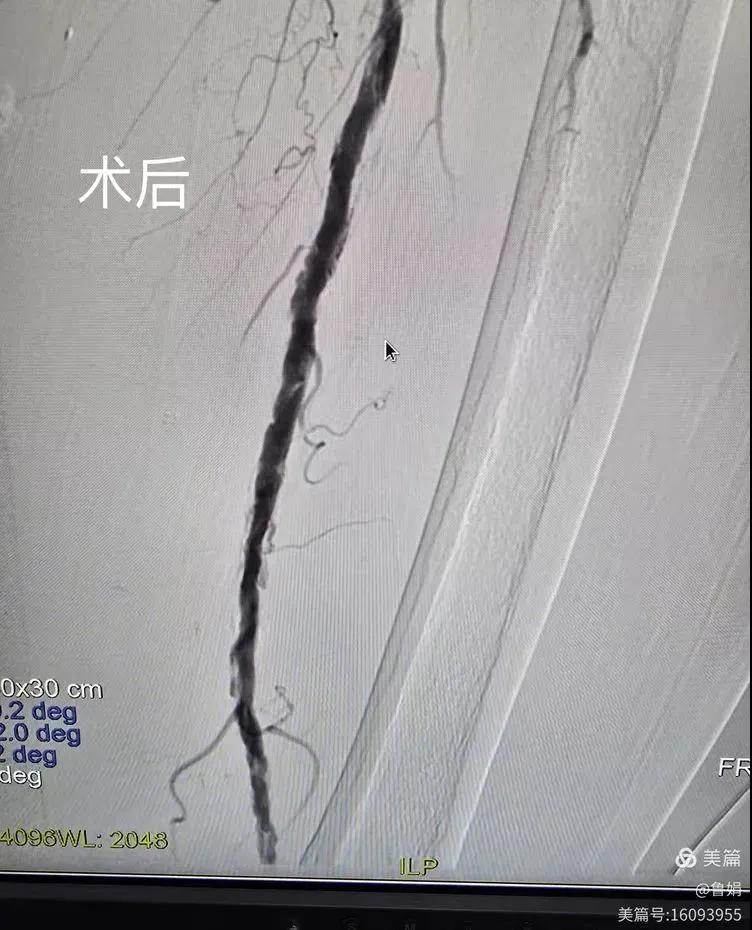

據(jù)悉,該患者,女,73歲,下肢動(dòng)脈硬化閉塞癥,“以靜息痛,間歇性跛行”入院,CTA評估:股淺動(dòng)脈,腘動(dòng)脈間斷性多段重度狹窄,外二科血管外科團(tuán)隊(duì)根據(jù)患者病情,結(jié)合檢查結(jié)果,經(jīng)過科室會(huì)診后,決定對該病人行介入治療。手術(shù)由周創(chuàng)業(yè)副主任與北大一院血管外科專家郭宏杰教授聯(lián)合開展,對股淺動(dòng)脈,腘動(dòng)脈重度閉塞段行血管開通+藥涂球囊擴(kuò)張成形,術(shù)后狹窄明顯緩解,血流恢復(fù)!